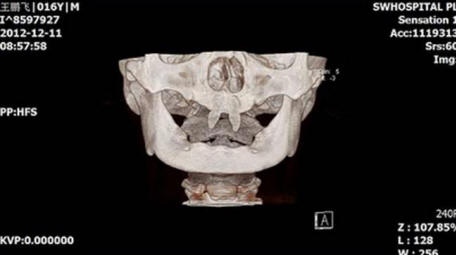

3. Najstnik je zrasel svoje vampirske zobe

Kitajcu je zrasel dva zelo ostra sprednja zoba zaradi česar je videti kot vampir. Decembra 2012 mati Wang Hui je sina Wang Penfei odpeljala v lokal bolnišnica za pregled. Chongqing Municipal Boy After rojstvo zelo slabo raste in v njegovih ustih sta se pojavila dva ostra fang.

Wang Hui je poskušal ugotoviti razlog za pojav tega sina nenormalne formacije in obiskali nešteto zdravniki, a ni prineslo veliko uspeha. Zdravniki iz V jugozahodni bolnišnici pravijo, da je mogoče storiti sina operacijo šele, ko postane odrasla oseba.